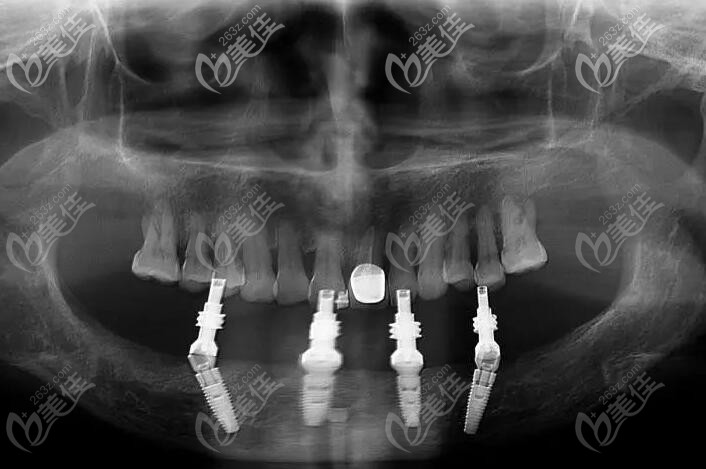

allon4/6半口即刻负重种植牙,半口种植4到6颗植体,可以恢复半口咬合力,也适合牙槽骨条件差的人,可以不用植骨粉,而且当天戴临时牙冠就能吃东西,此价格一般在6-16万左右。

下半口用allon4种植的CT照片▼